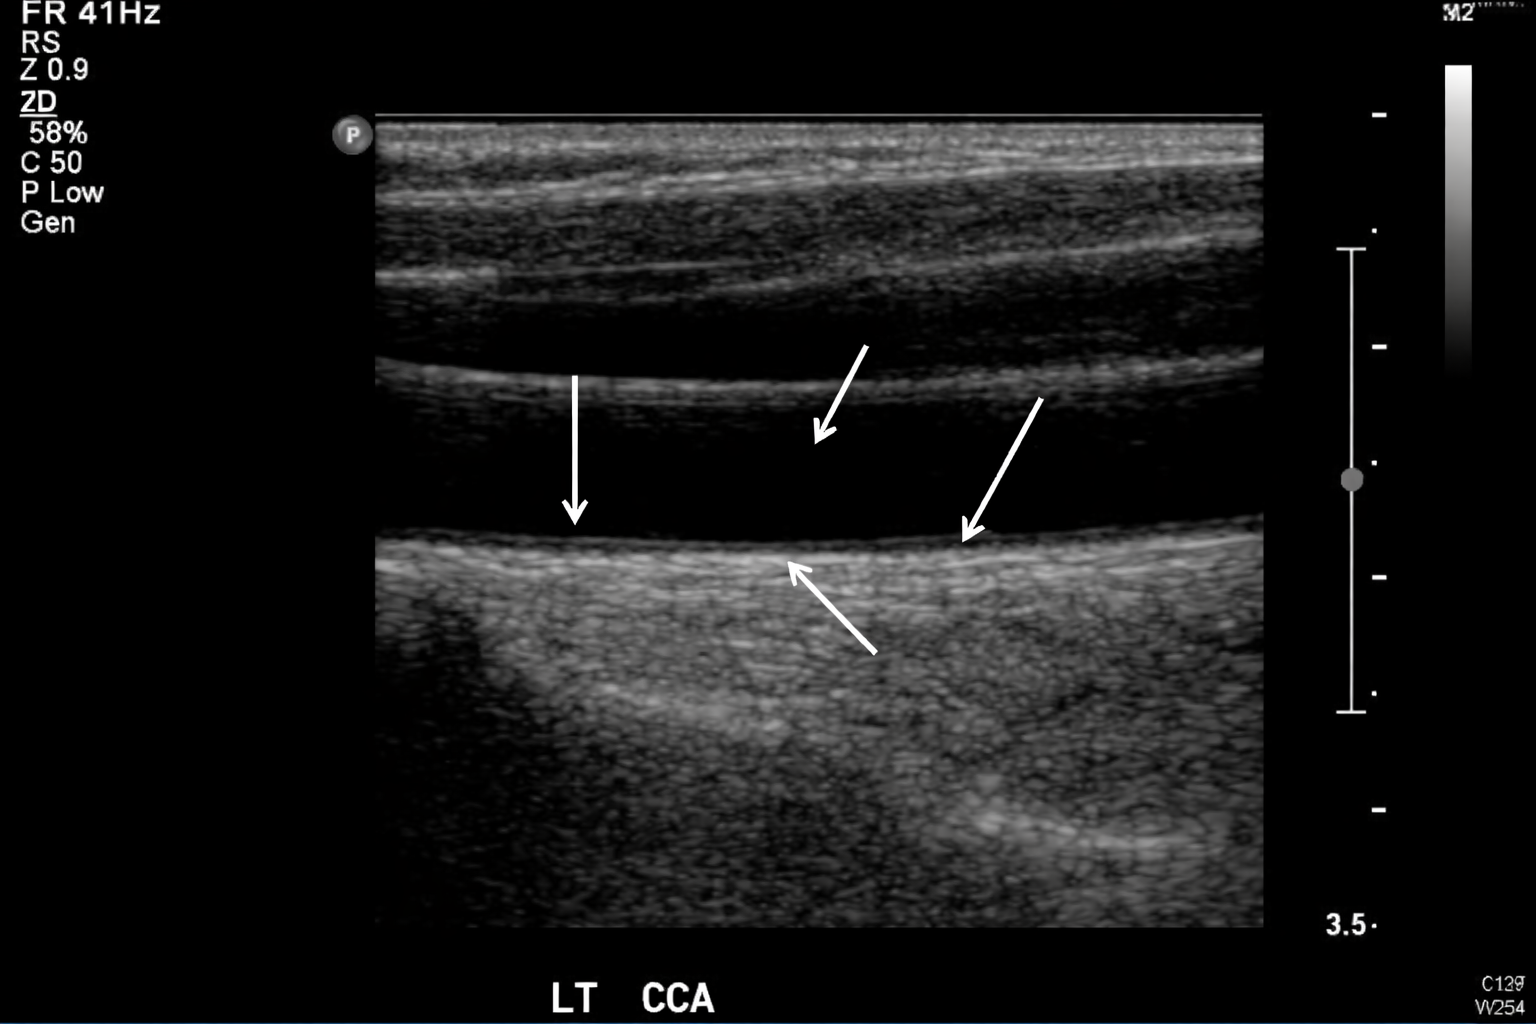

Label the anatomy of this Carotid Artery